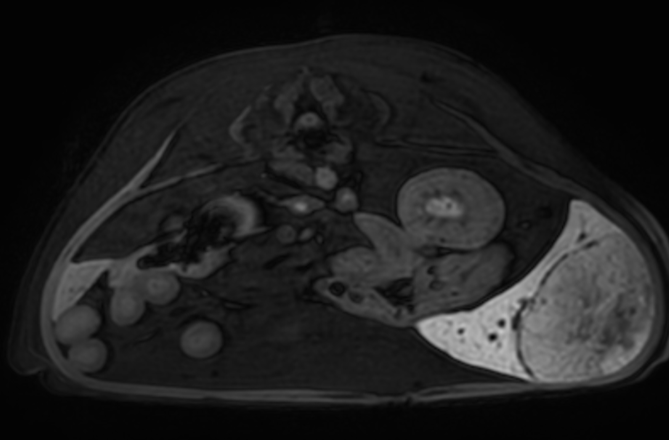

04복부 MRI

· 간, 골반강 평가

03복부 CT

· 간, 비장의 종양을 포함한 실질 변화 및 혈관기형(PSS)의 평가

· 소화기, 비뇨기 실질장기의 평가(종양, 이물, 염증 등)